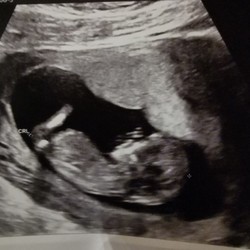

Ik gebruik die van de holland en barret en ze zijn mijn beste vriend. Ik neem er 2 per dag omdat ik anders wel misselijk werd naar 14 uur ongeveer. Sinds 2 weken niet meer misselijk. Inmiddels bijna 8 weken zwanger